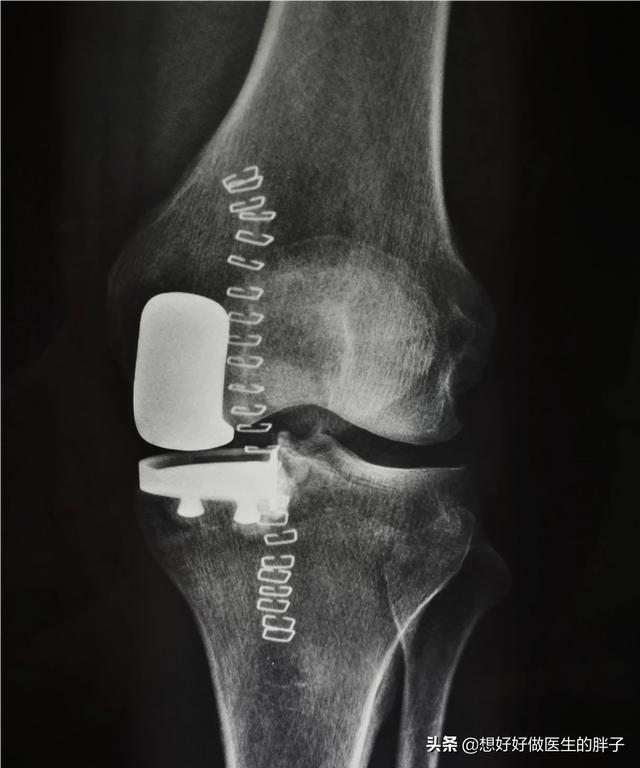

第一,当骨刺形成的过大,或者是形成的范围过广,就会影响到患者关节活动的屈伸范围,并导致疼痛。尤其是在一些比较大的关节,比如膝关节。在临床上因为膝关节骨质增生,进行手术或者保守治疗的患者是往往是最多的。

骨刺的治疗首选还是要以保守治疗为主,有很多患者说,那医生您不能将这些骨刺手术切除吗?答案是:可以切,但要看切除后会否解决患者的问题,比如严重的膝关节骨质增生,那么医生完全可以通过关节置换的办法将骨刺切除掉,将导致问题的软骨面儿也切除掉,换上金属的表面,这样就会彻底解决患者的问题。但是有一些患者达不到做这么大手术的程度,而且即使将一些小的骨刺切除掉,很有可能在1~2年之后会重新长出新的骨刺,那么相当于做无用功。而且有一些骨刺周边出现的症状是由于骨刺刺激到了周边的软组织产生了炎症,医生通常可以控制住这些炎症,症状也就会随之减轻,那么就完全没有必要将骨刺切除掉。

第六,手术治疗。手术治疗是医生和患者都不愿意进行的最后一步。但是有一些患者的病情确实达到了需要关节置换才能解决这些骨刺导致问题的程度。那前面已经说到了,例如肩关节、髋关节以及膝关节,如果是严重的骨质增生、严重的软骨磨损,患者会出现明显的关节活动受限,同时会伴有夜间痛以及休息痛,有的患者被折磨的痛不欲生,那么面对这种情况,可能手术治疗是最佳的治疗办法【7】。以往的手术就是比较单纯的关节置换手术,但是现在也重视到保膝手术治疗的发展,现在也有很多医生会根据患者的病情进行部分关节置换或者是截骨矫形等保膝手术治疗来尽量保留患者关节良好的部分,只处理有问题的部分。